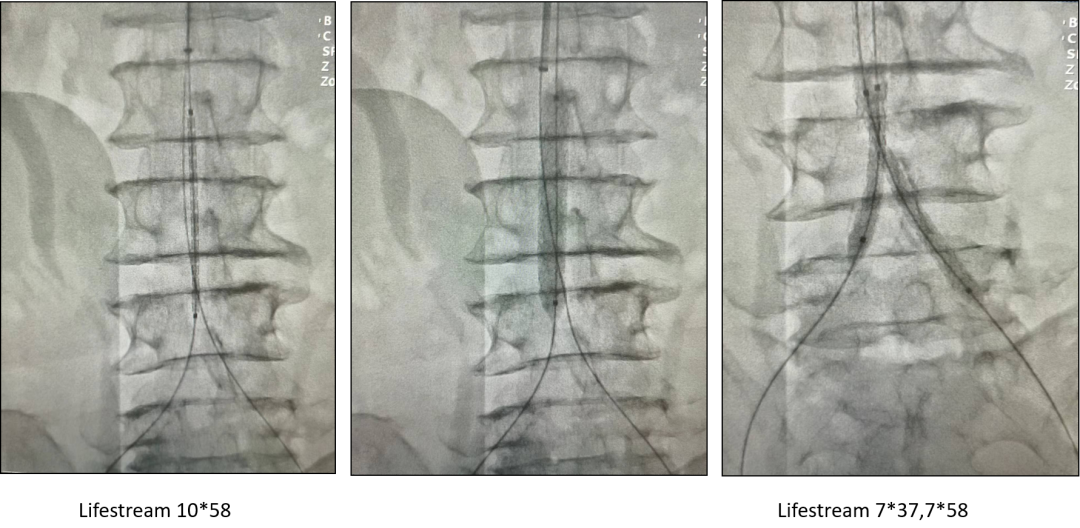

“小”对吻

CERAB

“长”平行

“假”CERAB:CUFF+双髂BMS或CUFF+双髂自膨式覆膜支架。